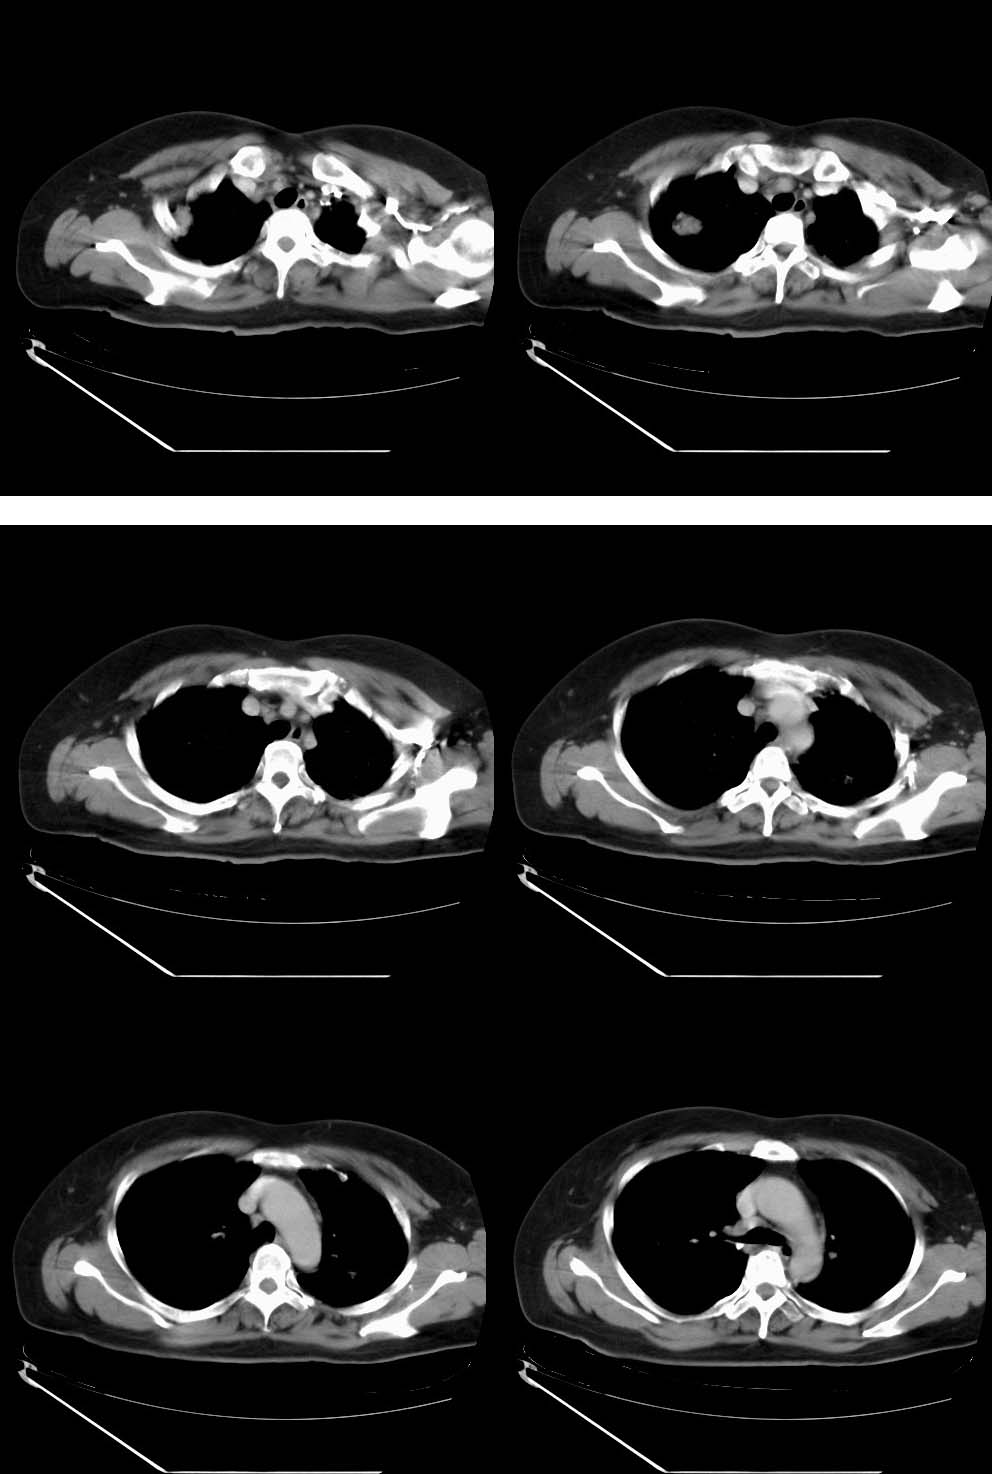

女,64岁,2月前体检透视发现右上肺阴影,未行任何治疗。无咳嗽咳痰、胸痛胸闷症状。生化检查(血象、防癌全套等)均未示异常。轻—中度强化。

见点状钙化的卫星灶,左上肺也有点状钙化灶。

右肺上叶结核瘤。

右上肺占位考虑结核球,左上肺病灶有钙化,考虑慢性炎变,所以双肺改变考虑结核

右上病变有脂肪及钙化,考虑良性病变,错构瘤可能性大,左上陈旧性tb。

右肺上叶肿块,边缘毛糙,未见钙化,考虑周围型肺癌,左肺斑点状及索条状高密度,考虑结核。

肿块内有钙化,虽无明确卫星病灶,还是考虑结核球可能大,随访除外新生物。

另左上肺纤维硬结灶。

右上肺结节有分叶征、但似可见细小的沙粒状钙化阴影,邻近胸膜有增厚而不是胸膜凹陷证。结节有轻中度强化。这些都是矛盾的。

拟诊:瘢痕ca可能性大。